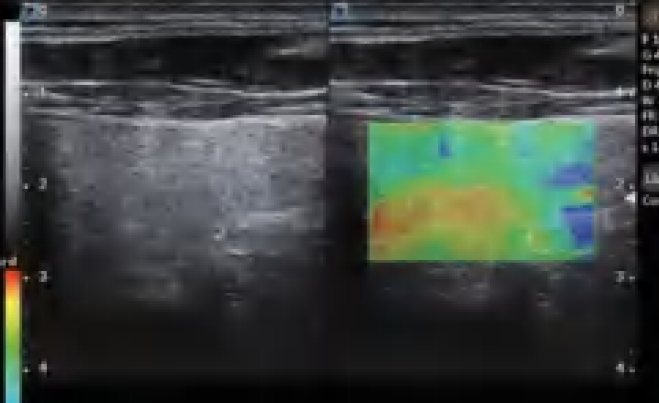

El DW-L50 Exp, impulsado por la avanzada plataforma de ultrasonido ST-U, ofrece imágenes ultra claras en todo momento. Con una movilidad y adaptabilidad sobresalientes, funciona de manera fiable en diversos entornos clínicos complejos. Su introducción permite que más instituciones médicas accedan a tecnología de ultrasonido rentable y de alto rendimiento.